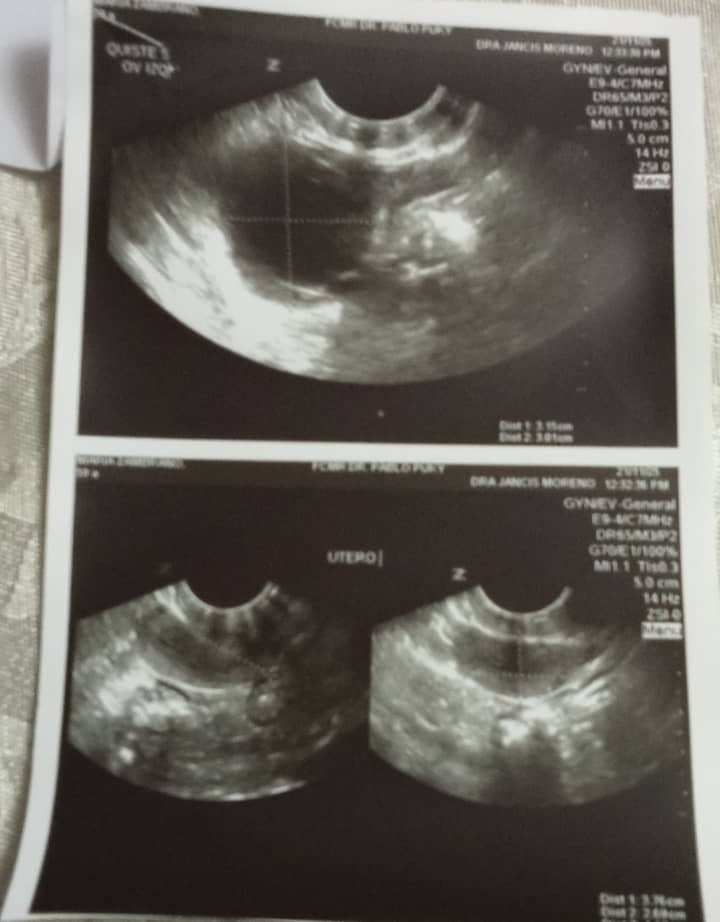

María Lourdes tiene un diagnóstico de quiste en útero y nódulo mamario izquierdo.